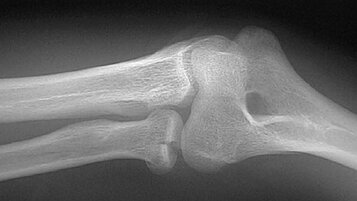

Se si sospetta una lesione con coinvolgimento dell’osso, il primo esame da eseguire è la radiografia standard. Per meglio definire fratture complesse e con eventuale coinvolgimento articolare, la tomografia computerizzata (TAC) offre la maggiore quantità di dettagli.